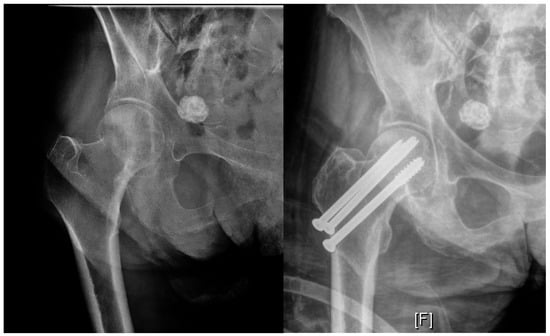

2.2. Nondisplaced Femoral Neck Fractures: Internal Fixation vs. Arthroplasty

2.3. Displaced Femoral Neck Fractures: Internal Fixation vs. Arthroplasty